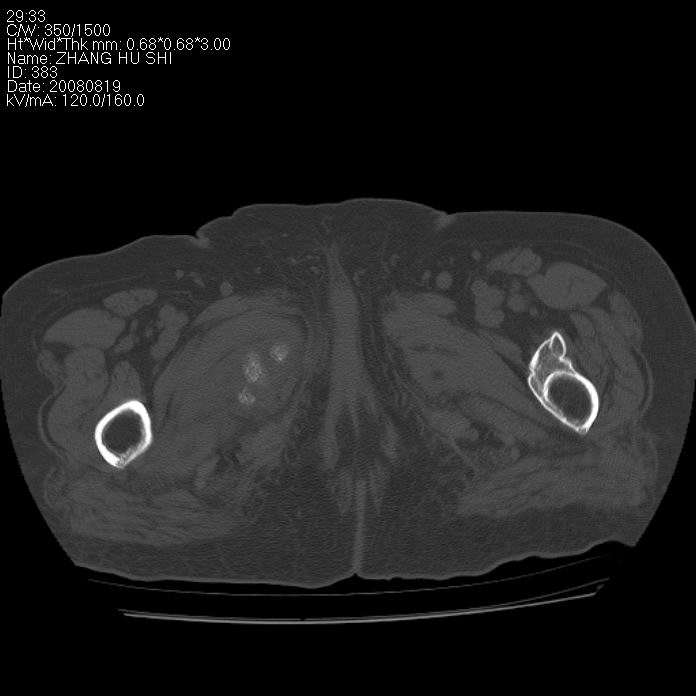

标题: CT15287:女 93岁 右髋关节疼痛 原左侧粗隆间骨折 CT发现右耻 [打印本页]

标题: CT15287:女 93岁 右髋关节疼痛 原左侧粗隆间骨折 CT发现右耻

支持转移

支持转移并周围软组织侵犯右闭孔内肌侵犯,但tb不能完全除外。